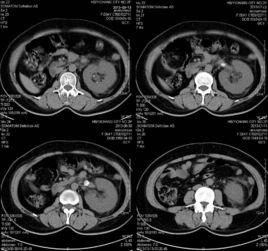

CT表現:腎膿腫表現因病期不同而有所差異。在早期炎症期,膿腫尚未局限化,表現為腎實質內略低密度腫塊,增強檢查可有輕度不規則強化;在膿腫成熟期,表現為類圓形均一低密度灶,邊緣清晰或模糊,周邊有厚度不一的略高密度環圍繞,增強檢查呈明顯環狀強化,代表膿腫壁,而中心低密度區無強化,為膿腔,部分膿腔內還可見低密度氣體影。腎膿腫感染蔓延至腎周間隙時可見腎周脂肪密度增高。當合併有腎周和腎旁膿腫時,表現腎周和腎旁脂肪間隙消失,代之以混雜密度腫塊,內可有小氣泡影,增強檢查呈規則或不規則單發或多發環狀強化。

腎膿腫結合臨床和實驗室資料,診斷多無困難。CT檢查可清楚顯示腎輪廊、腎周圍間隙及與其鄰近結構的關係,可指導臨床治療。CT對臨床表現不典型以及早期膿腫診斷困難,不易與腎細胞癌鑑別,需結合臨床、短期隨訪甚至細針抽吸活檢來明確診斷。總的說來,不論膿腫的位置及範圍如何,均會導致病側腎臟不同程度的功能障礙,表現為CT強化程度弱於正常腎。這是腎臟炎性病變的一個重要特徵。MRI在腎膿腫檢查中有一定意義,但並非常規檢查。